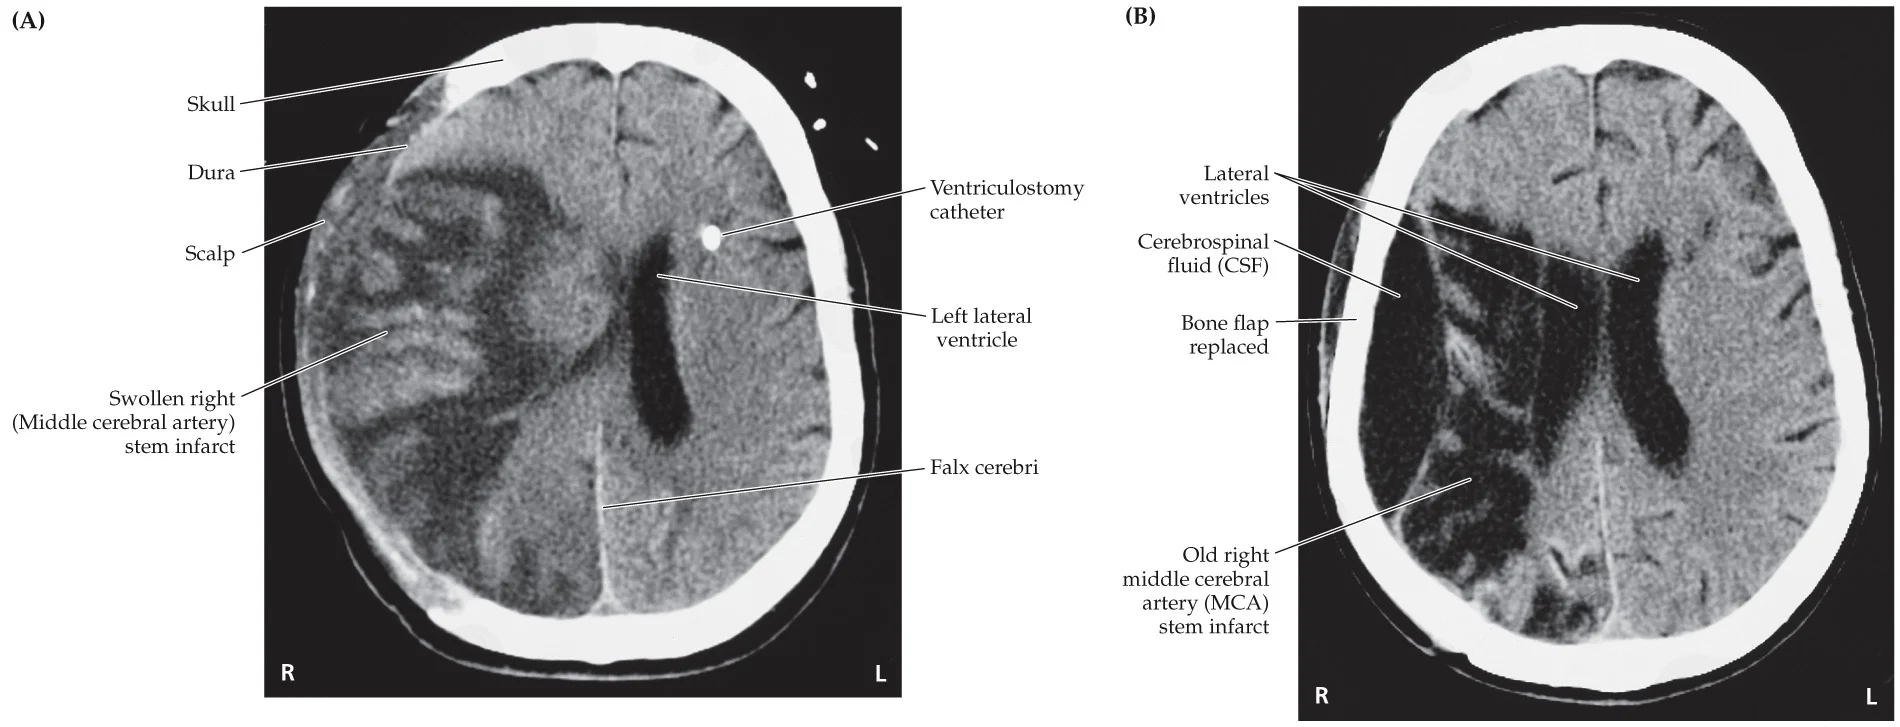

The patient was working in his yard removing weeds on the day of admission when his wife noted an episode of slurred speech around 2:00 p.m., which then improved. He was fine until 4:45 p.m., when he suddenly developed right-sided weakness, slumped to the right, could not speak, and had a leftward gaze deviation. His wife called an ambulance. Past medical history was notable for hypertension

Left MCA stem infarct